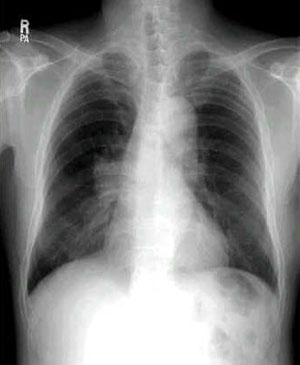

X-선 소견 3가지

- 폐문-종격형 : 빈도가 높으며 감별 진단상으로 중요.

폐문림프절 및 종격의 림프절이 종대한 type으로 폐내 병소는 불확실

말초형 : 국한성 종류 및 침윤영

간접, 혼합형 : 무기폐, 폐색성 폐렴,폐기종(emphysema), 흉수등 소견